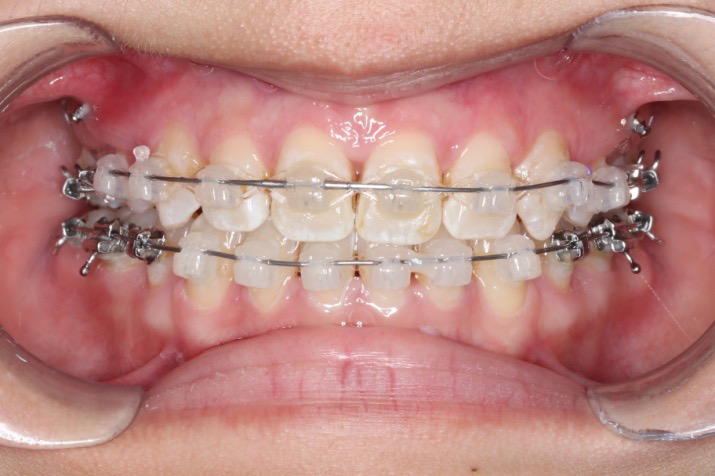

2018.11.14  术后磨牙尖牙I类关系,中线齐,覆合,覆盖正常

Post-TXPRE-TXPost-TXNormFMIA°47°57.555.0SNA°77.7°76.883.0SNB°70.2°73.780.0ANB°7.5°3.13.0FMA° 29.828.026PFH/AFH70.5°65.970Z Angle°50.3°64.477U1-FH113.0103.7110.0 IMPA°103.291.197.0U Lip tos’ line6.3 mm3.25.0L Lip to s’ line3.9 mm1.03.0OP-FH1212.615